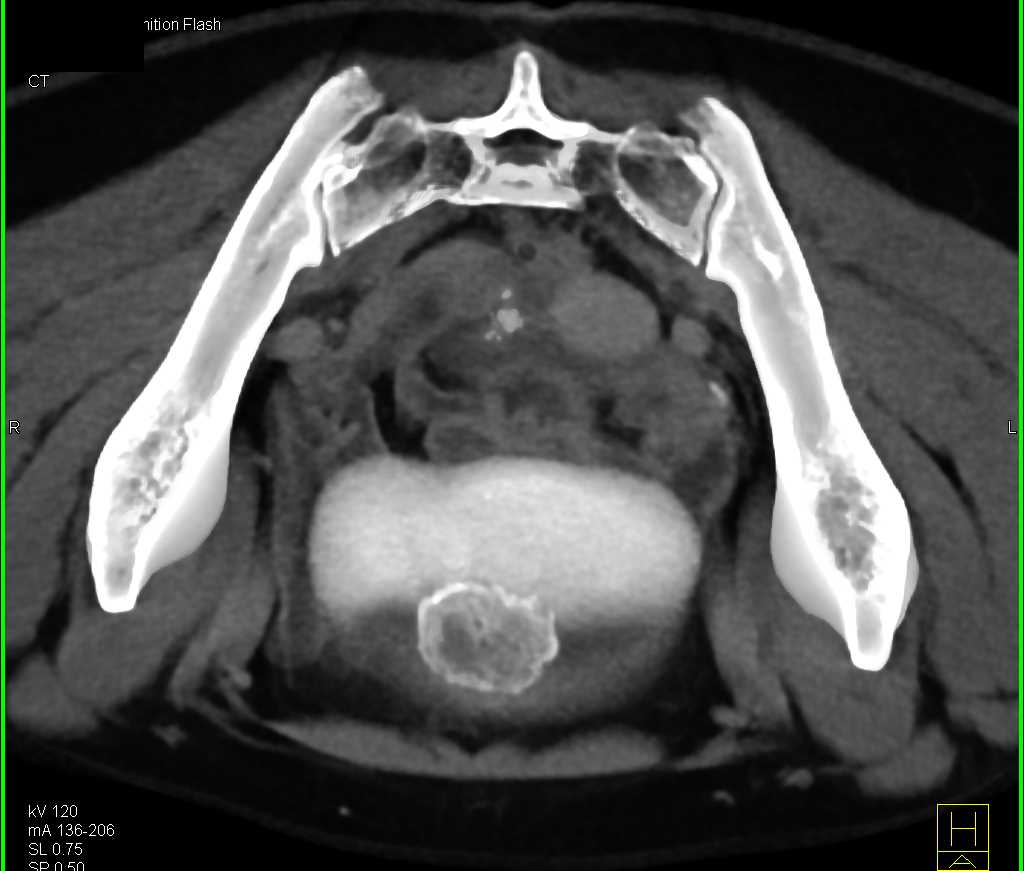

Urachal Carcinoma of the Bladder